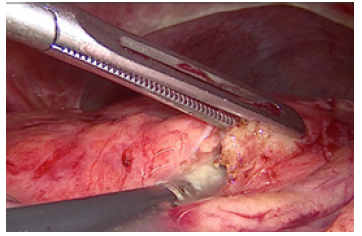

In ten cases we performed laparoscopic cholecystectomy with debridement of pancreatic necrosis. For 18 patients we explored the CBD by choledoscope and extraction of stones was done. The operation was finished with placement of T- tube drainage by laparoscopic approach. In 7 cases was accomplished percutaneous drainage of WOPN under US-control. For eight patients a two-stage procedure was applied. The first step was a placement of percutaneous biliary drainage under US-control and C-arm control. The second step was laparoscopic necrosectomy. A temporary loop ileostomy was performed in 5 cases because of bowel paralysis around the pancreas, paralytic ileus, abdominal distention and worsening of the patients’ condition. Debridement by laparoscopic access was accomplished by transgastric approach or gastrocolic access to enter the lesser sac. Applying a gentle blunt removal of necrotic tissue around pancreas, we take care of blood vessels around the pancreas, and we usually use a bipolar coagulation in case of bleeding from vital pancreatic tissues. We always take a sample from infected tissues for culture and subsequent precise antibiotic treatment (Figure 3).